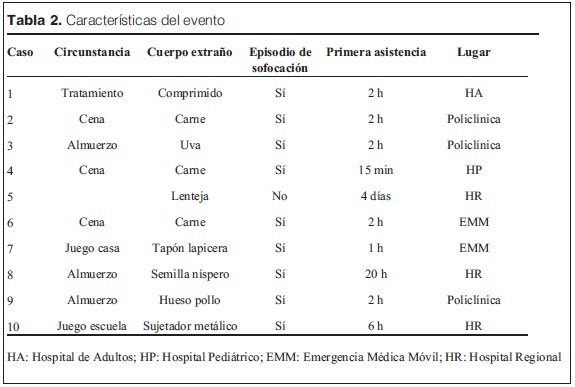

En cuanto a las características del evento (tabla 2) en siete de los casos el material aspirado fue de sustancias orgánicas (carne, uvas, lentejas, semillas, cartílago), que ocurrió durante la alimentación (almuerzo, cena).

En tres ocasiones fue de material no orgánico (comprimido, tapa de bolígrafo, sujetador metálico), uno solo de ellos radioopaco.

En los casos en los que el episodio de sofocación fue presenciado por un adulto, se generó una consulta dentro de las primeras 24 horas. En el caso en que no estuvo presente (caso 5), la consulta se produjo después del tercer día.

Nueve niños estaban en su hogar de alojamiedeleonardisdaniel@gmail.comnto, y uno en la escuela.

La primera asistencia fue en hospital de adultos (caso 1), policlínica (casos 2, 3 y 9), hospital regional (casos 5, 8 y 10), emergencia móvil (casos 6 y 7) y en HP (caso 4).

Con referencia a las características clínicas y tratamiento efectuado (tabla 3) vemos que en seis casos se efectuaron maniobras básicas para desobstruir la vía aérea, ya sea manuales (barrido de la boca con el dedo) por parte de familiares y/o personal de la salud, o la clásica maniobra de Heimlich.

La imagenología realizada consistió en radiología de tórax previa en cuatro pacientes, y TAC en uno. Las radiografías mostraron signos indirectos compatibles con aspiración de CE: en un caso tórax asimétrico (figura 4); en el caso 6 atelectasia (figura 3); en el caso 10 clip metálico (figura 2); y en dos fue normal (casos 7 y 8).

En el caso 8 se realizó TAC que localizó el CE en la carina (figura 5).

La eliminación espontánea del CE se produjo en dos oportunidades (casos 1 y 3); en otros dos se extrajo al momento de la consulta en el DEP del carrefour aerodigestivo bajo sedoanalgesia (casos 2 y 4).

En seis ocasiones la extracción se realizó con broncoscopio rígido bajo anestesia general, cuatro de ellas de bronquio fuente derecho (BFD) y dos de bronquio fuente izquierdo (BFI).

Todos los CE fueron expulsados o extraídos entre dos horas y cuatro días del episodio de aspiración, con una mediana de seis horas.